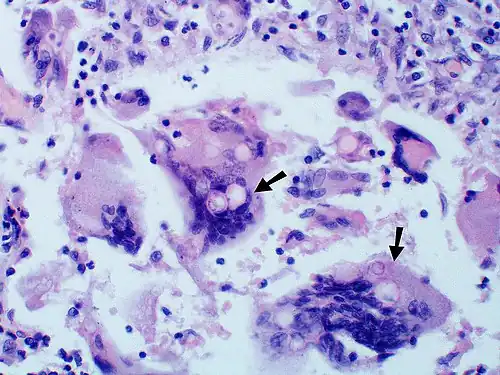

-

Granuloma with early suppuration. The fungal organisms are difficult to recognize at this low magnification. -

Large yeast-like fungi seen within giant cells at arrows. -

Large yeast-like fungi seen within giant cells at arrows. Budding yeasts in the cytoplasm of giant cells at the arrows. Broad-based budding and double-contoured cell walls are seen in the giant cell in the center are characteristic of Blastomyces dermatitidis. -